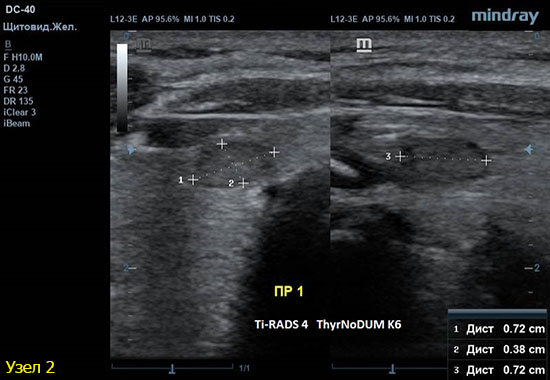

2) Узел у перешейка, не прорастает капсулу щитовидной железы (0 баллов), больше широкий чем высокий (0 баллов), не имеет кальцинатов (0 баллов), с ровным четким контуром (0 баллов), гипоэхогенный (2 балла), тканевой структуры (2 балла). Количество баллов 4, ACRTi-RADS4, ThyrNoDUMК6. Пункция не показана в связи с малым диаметром узла (более 1,5 см для Ti-RADS4), рекомендовано наблюдение.